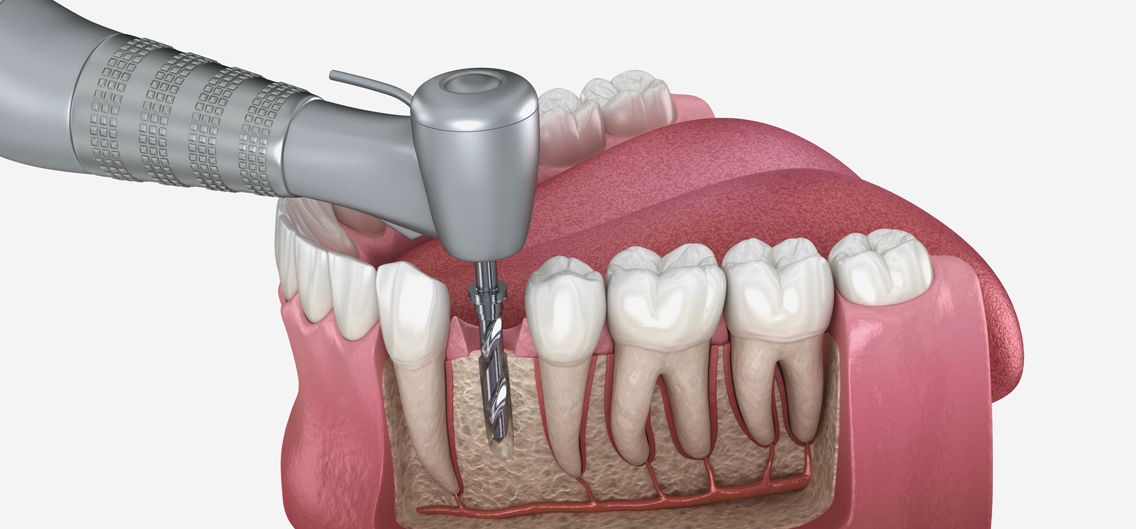

정밀 CT 촬영과 구강 검사를 통해 잇몸·뼈 상태를 확인하고, 개인에게 가장 적합한 임플란트 치료 계획을 세웁니다.

치조골에 임플란트 픽스처(뿌리 역할)를 정확하게 심는 단계로, 국소마취 하에 안전하게 진행됩니다.